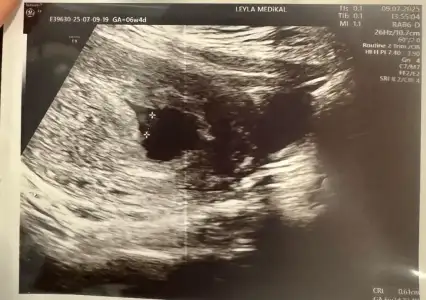

6 haftalik karından ultrasyon tahminde bulunabilir misiniz

Eklentiler

• IMG_20250312_112835.webp

IMG_20250312_112835.webp

31,3 KB · Görüntüleme: 70

• IMG_20250312_094215.webp

IMG_20250312_094215.webp

21,9 KB · Görüntüleme: 58

• IMG_20250312_094132.webp

IMG_20250312_094132.webp

44,2 KB · Görüntüleme: 73